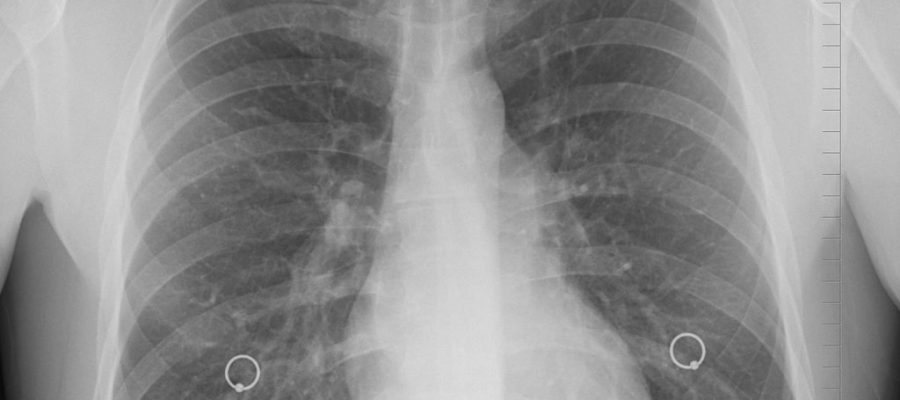

• Görüntüleme Testleri: X-ray veya MRI gibi görüntüleme testleri, kaburga pozisyonunu net bir şekilde görüntüleyebilir.